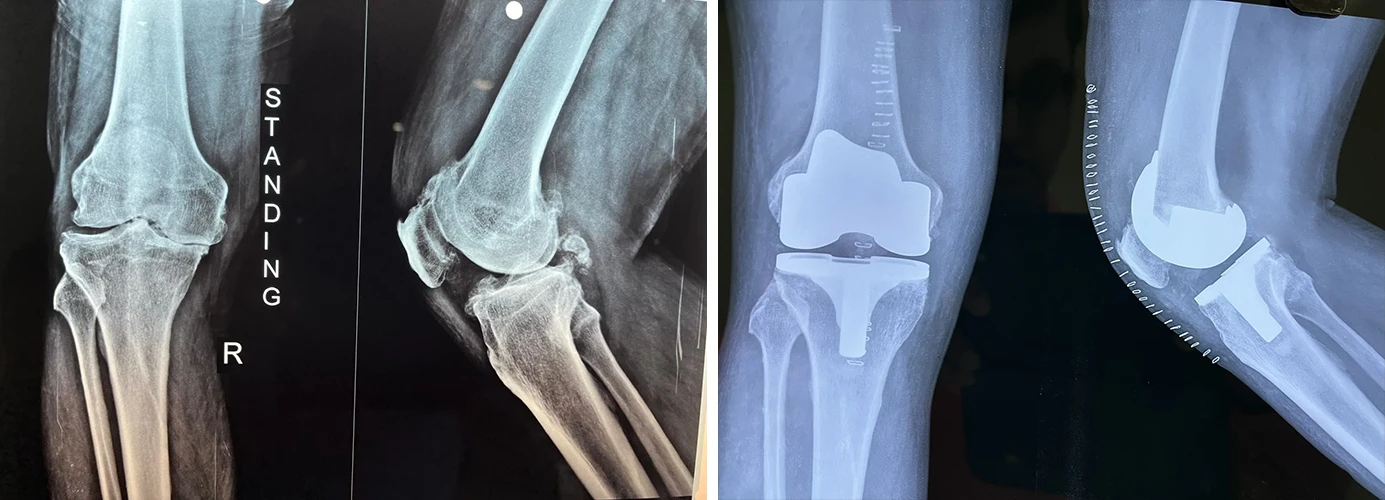

Total Knee Replacement

Are you having pain in your knees? Look no further, because Dr. Sanyal is the best choice for you. He specialises in total knee replacement surgery, offering you a solution to regain your mobility and live pain-free.

My mother was under Dr. Prasun Sanyal’s treatment. She was undergone the right knee replacement surgery six months ago. The operation was a success. She is perfectly alright. She can walk now normally . The previous pain before surgery has gone.

Dr. Sanyal is extremely professional and punctual. He cares his patients a lot. The best thing is that he always keeps contact with his patient.

We are preparing now for my mother’s left knee replacement surgery within two or three months and that obviously, under Dr. Sanyal.